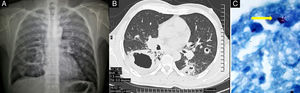

Caso clínicoPaciente masculino de 44 años, con GPA diagnosticada en abril de 2003 ante pérdida de peso, tos, episodios recurrentes de escleritis nodular, mononeuritis múltiple, nódulos cavitados en la TC de tórax (fig. 1A), proteinuria (50mg/dl), eritrocituria dismórfica y anticuerpos anticitoplasma de neutrófilo (cANCA) positivos. Recibió glucocorticoides y 7 bolos de ciclofosfamida, con metotrexato como terapia de mantenimiento.

En julio de 2009 tuvo una recaída, con tos productiva sin hemoptisis, mononeuritis múltiple, proteinuria (50mg/dl), hematuria dismórfica y elevación de la proteína C reactiva (16,7mg/dl). La tomografía de tórax mostró una imagen sugerente del signo de la media luna (fig. 1B), característico de aspergiloma1. Para descartar la infección, se realizó la biopsia de la lesión, que informó granulomas no caseosos (actividad de la enfermedad). Los cultivos y las tinciones descartaron infección micobacteriana y micótica (fig. 1C). Recibió nuevamente ciclofosfamida (7 ciclos), metilprednisolona, y de mantenimiento, azatioprina.